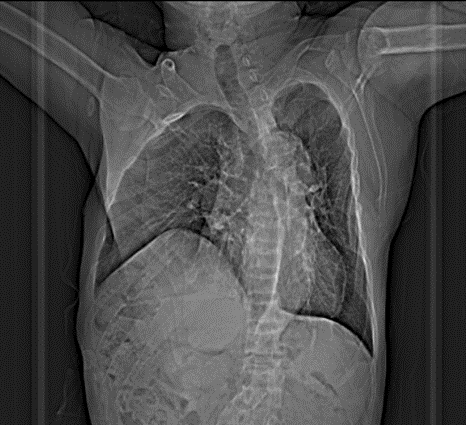

入院后完善相关检查,提示覃老师存在严重骨质病变、血管明显钙化。

胸片摄片提示脊柱侧弯明显